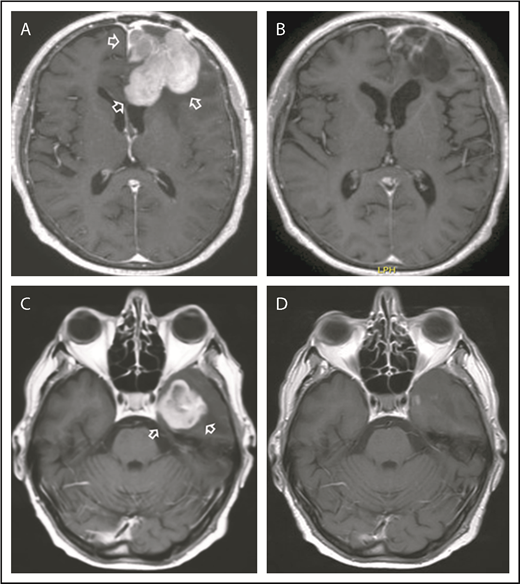

Examples of responses to R-CHOP preceded by NGR-hTNF. (A) Gadolinium-enhanced T1 weighted scan shows a large homogeneous enhancing lesion in the left frontal lobe (arrows) in a 62-year-old woman at the second relapse after high-dose methotrexate and after salvage high-dose ifosfamide-based therapy; disease was refractory to previous lines. (B) Tumor regression after 2 courses of experimental treatment. (C) Gadolinium-enhanced T1 weighted scan shows a large enhancing left temporal lesion (arrows) in a 65-year-old man at the second relapse after high-dose methotrexate and after salvage whole-brain irradiation. (D) Tumor regression after 2 courses of experimental treatment.